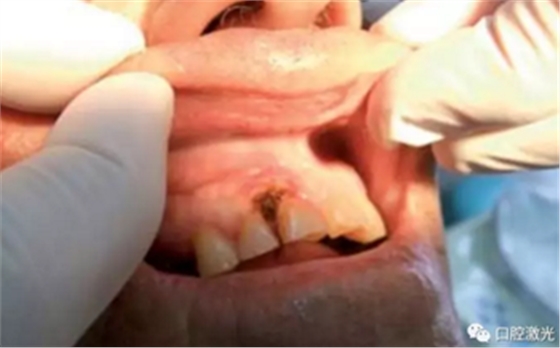

在治疗前,患者、医生及助手均佩戴正确的防护眼镜,并且对患处进行拍照记录。随后使用2%的利多卡因 1cc进行浸润麻醉。激光器设置完毕后,采取外切的手法,利用镊子将龈瘤拉伸后,从其根部进行外切。手术后无需缝针,并对切除物进行病理学检查。检查结果确认为纤维瘤。整个手术过程通常为4至6分钟。建议患者术后冰敷以减少水肿发生。

术后1周、4周、6个月以及1年对患者进行追踪观察。1周复诊时,重点了解疼痛、出血以及水肿的情况。其结果为没有出现上述情况。所有的患者都可以术后立即恢复正常的生活、学习、工作活动。并且,术后没有使用止疼药和消炎药。在4周时,评估伤口的愈合情况,所有的患者都恢复很好,没有出现并发症现象。在6个月至1年期间,没有出现任何形式的复发。因此,患者对激光手术的效果评价十分高。